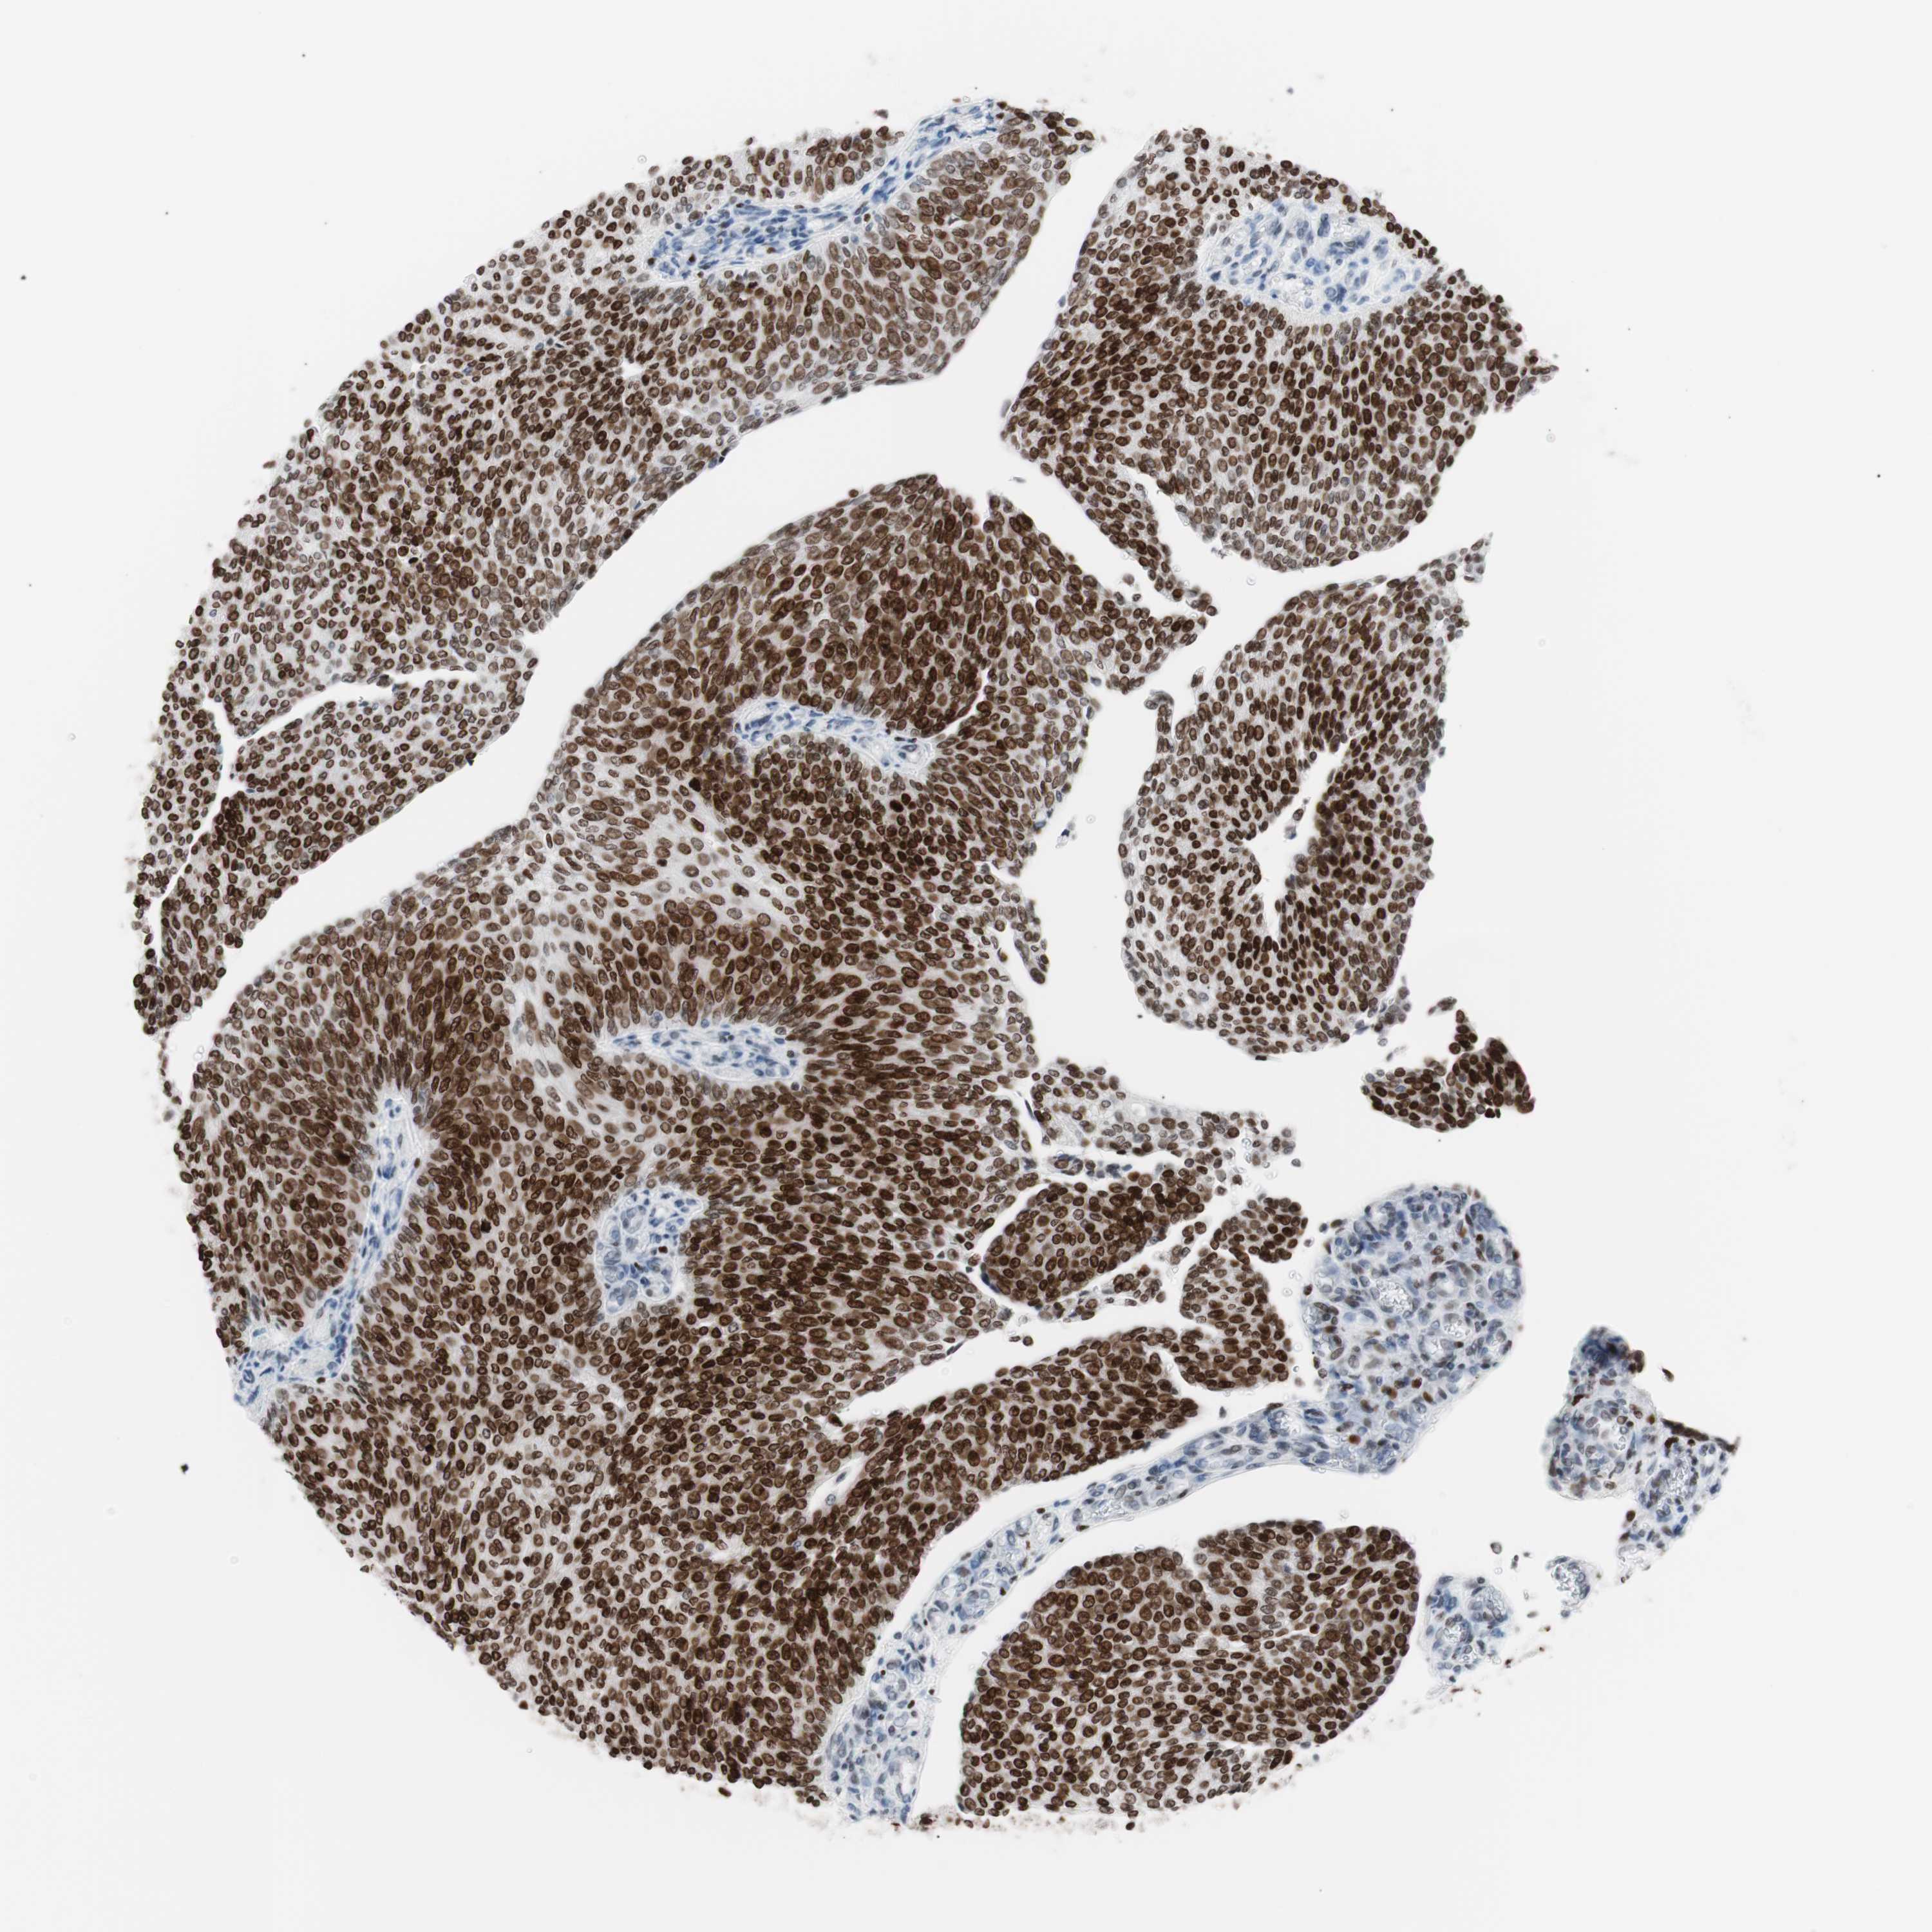

UROTHELIAL CANCER - Protein expressioni

A mouse-over function shows sample information and annotation data. Click on an image to view it in a full screen mode. Samples can be filtered based on level of antibody staining by selecting one or several of the following categories: high, medium, low and not detected. The assay and annotation is described here.

Note that samples used for immunohistochemistry by the Human Protein Atlas do not correspond to samples in the TCGA dataset.

Antibody stainingi

Antibody staining in the annotated cell types in the current human tissue is reported as not detected, low, medium, or high, based on conventional immunohistochemistry profiling in selected tissues. This score is based on the combination of the staining intensity and fraction of stained cells.

Each image is clickable and will lead to virtual microscopy that enables deeper exploration of all samples and also displays staining intensity scores, fraction scores and subcellular localization as well as patient and tissue information for each sample.

Antibody CAB004213

Staining

High

Strong

Quantity

Location

Urothelial carcinoma, Low grade

Urothelial carcinoma, High grade